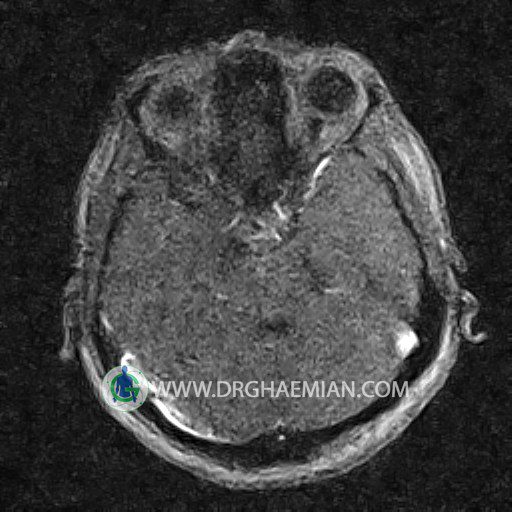

ام آر وی یک روش تصویربرداری دقیق و غیر تهاجمی است که برای معاینه ورید های بدن و ارزیابی سلامت رگ ها استفاده می شود. ورید ها خون را از اعضای بدن به قلب باز می گرداند تا دوباره اکسیژن و مواد مغذی به خون داده شود. ام آر وی جریان خون را ارزیابی و موارد غیرعادی مضر مانند لخته های خونی را شناسایی می کند. در این کیس ترومبوز دیواری مغز در سینوس عرضی راست و ترمبوز جزئی در سینوس عرضی چپ دیده می شود.

Images of the venous cranial vessels demonstrates a superior sagittal sinus of normal caliber with normal arrangement of draining superficial cerebral veins.

The great cerebral vein Galen inferior sagittal , straight sinus and left sigmoid sinus appear normal.

The right sigmoid sinus present a normal caliber.

The other evaluable deep cerebral veins , basal and labbe are normally developed and patent.

The other evaluable portions of the neurocranium show no abnormalities.